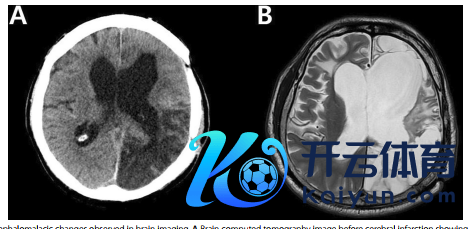

58岁时,患者因左侧颈内动脉阻塞发生急性脑梗塞,脑梗塞后左侧顶枕区脑软化变化扩张至扫数这个词左大脑半球(图2)。令东谈主不测的是,而后患者日常癫痫发作竟总共住手,仅服用拉科酰胺(100mg bid),且已保执3年无癫痫发作,活命质料也未因仍需轮椅援助而显贵着落。

图2 脑影像学搜检中不雅察到的脑软化变化

注:A 卒中前的CT图像,显现变化主要集合在左侧顶枕区。

B 卒中后的脑部磁共振成像(MRI)图像,显现变化累及扫数这个词左大脑半球。